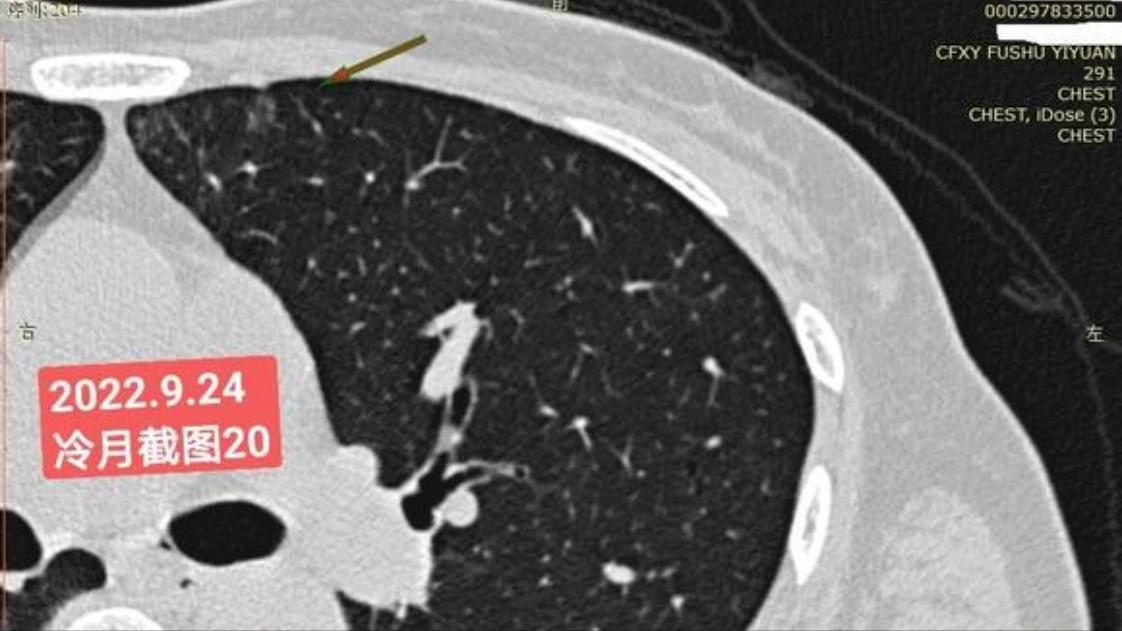

我是21年7月做肺部CT,报告给报出0.5厘米肺结节。(但大夫说,20年就已经有那个肺结节了,因为小,报告没给报)。自发现肺结节后,吃了四个月中药,结节没有缩小,反而增大了。今年8月1日开始到现在,又吃了近两个月的蒙药了。 结节还是没有缩小,反而在增大。21年7月到现在,复查过3次肺部CT了。结节一直在增大。最近一次复查时间是2022年9月24日。

上次找戴主任贴吧咨询过,主任说我右肺下叶那个结节高危,距离上次CT,到现在三个月复查肺部CT。所以9月24日又复查做了肺部CT。

右下肺结节高危,肺窗已经到亚实性阶段CTR>0.5,纵膈窗可见实性,目前已经不属于异质混磨,而且PSN亚实性结节。